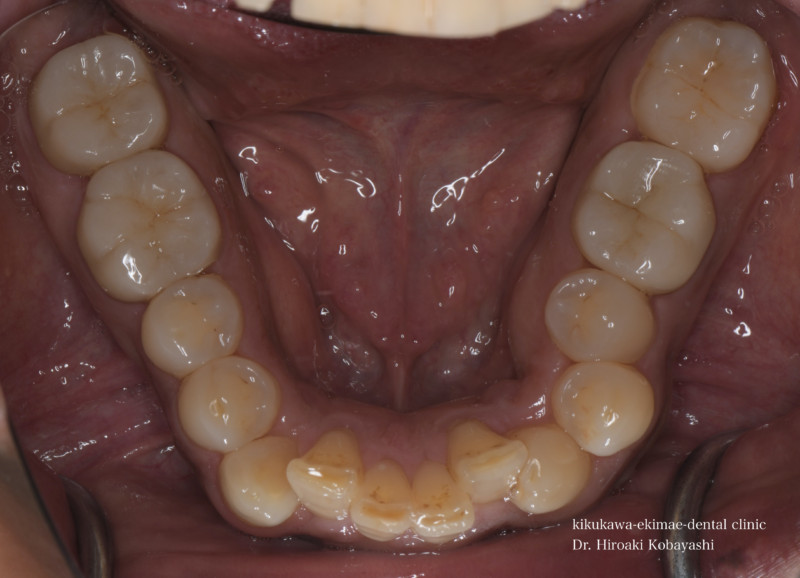

お口の問題は、細菌感染、噛み合わせ、唾液の質、セルフケアの質、食習慣など様々な問題が複合的に起こり、結果、穴があくという現象(虫歯)や痛みとして現れています。

歯は加齢と共に失う組織ではありません。適切な治療と予防管理を継続すれば生涯、歯を失うことはありません。義歯やブリッジ、インプラントの材料や技術がどんなに発達しようとも、まだまだ天然歯に勝るものはありません。